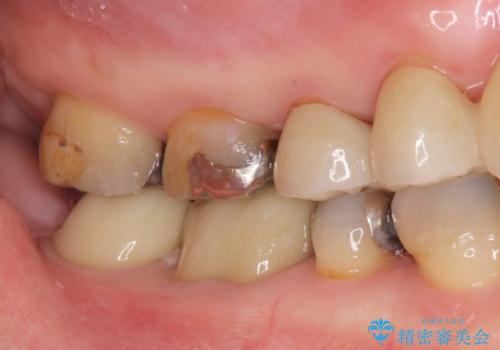

- メタルの詰め物がされている歯が欠けてしまった患者様です。

メタルを外すと中で虫歯が広がっていました。

拡大鏡下で虫歯を取り切った後、フルジルコニアクラウンにて治療しました。